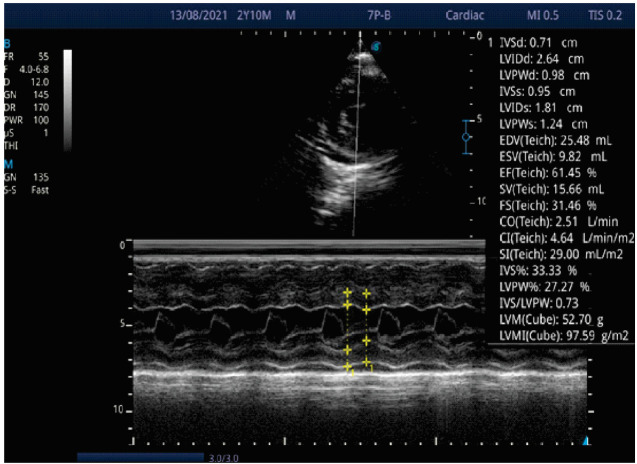

主动脉缩窄是一种梗阻性的先天性心脏缺陷,表现为上肢高血压。如果不及时治疗,主动脉缩窄可导致左心室功能障碍和脑血管病。由于其微妙的表现漏诊是常见的伴随并发症。这是一个病例报告,一个表面上健康的3岁男孩在轻微跌倒后陷入昏迷。他有上肢高血压,下肢脉搏几乎摸不到。脑部计算机断层扫描(CT)显示非外伤性出血性中风,超声心动图显示严重的左心室肥厚和主动脉严重缩窄。主动脉缩窄可表现为慢性上肢高血压患儿并发非外伤性出血性中风。幼儿常规血压测量可作为早期诊断的筛查工具。

Coarctation of the aorta is an obstructive form of congenital heart defects that presents with upper limb hypertension. If untreated, Coarctation of the aorta can lead to left ventricular dysfunction and cerebral vasculopathy. Missed diagnosis due to its subtle presentation is common with attendant complications. This is a case report of an apparently healthy 3-year-old boy who lapsed into a coma after a trivial fall. He had upper limb hypertension and the pulses in the lower limbs were barely palpable. Brain computed tomography (CT) revealed non-traumatic haemorrhagic stroke and echocardiography showed severe left ventricular hypertrophy and severe coarctation of the aorta. Coarctation of the aorta can manifest as chronic upper limb hypertension in children with complicated non-traumatic haemorrhagic stroke. Routine blood pressure measurement in young children can serve as a screening tool for early diagnosis of the condition.